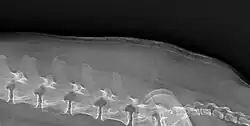

Cushing's may cause a breakdown of dermal proteins, causing shiny and thin skin, this can lead to secondary infection and is pathognomonic of Cushing's.[2]